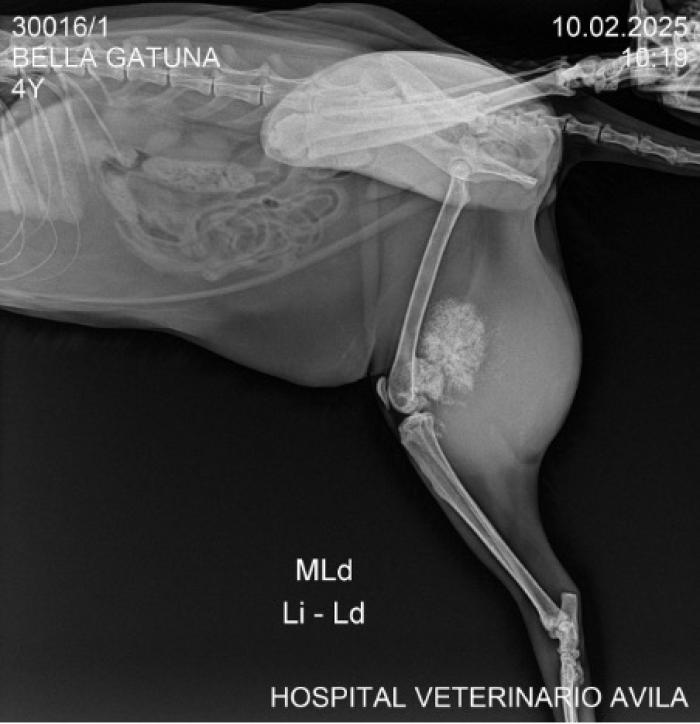

Radiografía

Se identificó una masa de densidad mineral heterogénea, con patrón mixto geográfico-agresivo, reacción perióstica desorganizada y mineralización en tejidos blandos adyacentes. Estos hallazgos son altamente sugestivos de una neoplasia ósea de origen condrogénico (Figura 1).